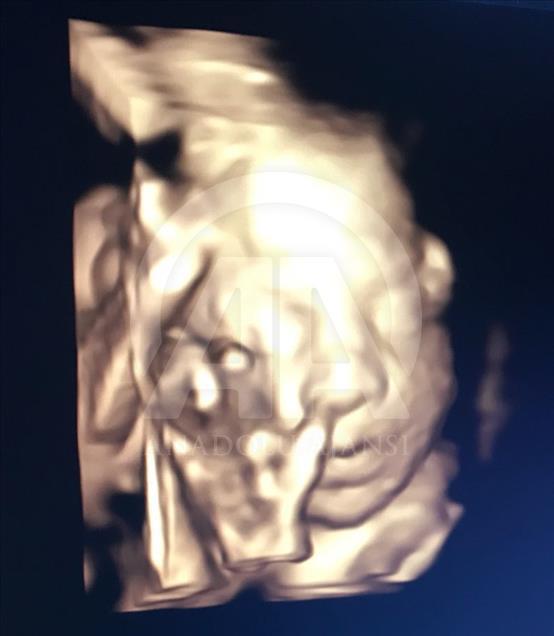

Anne karnındaki bebeklerin ilginç ultrason görüntülerini yakalayan ve bu görüntülerden özel bir köşe oluşturan kadın hastalıkları ve doğum uzmanı Doç. Dr. Gökalp Öner'in, yaklaşık 4 bin fotoğraflık koleksiyonu bulunuyor. Doç. Dr. Öner, AA muhabirine yaptığı açıklamada, sadece bir koleksiyon sahibi olmanın değil, anne ve babalara güzel bir hatıra oluşturmanın mutluluğunu da yaşadığını belirterek, "Doğumdan sonra aileler bizi ziyarete geldiği zaman kendi köşeleri olsun ve orada fotoğraf çektirelim istedik. Böylece, yaklaşık 4 bin ultrason fotoğrafına ulaştık." dedi. ( Müzahim Zahid Tüzün - Anadolu Ajansı )